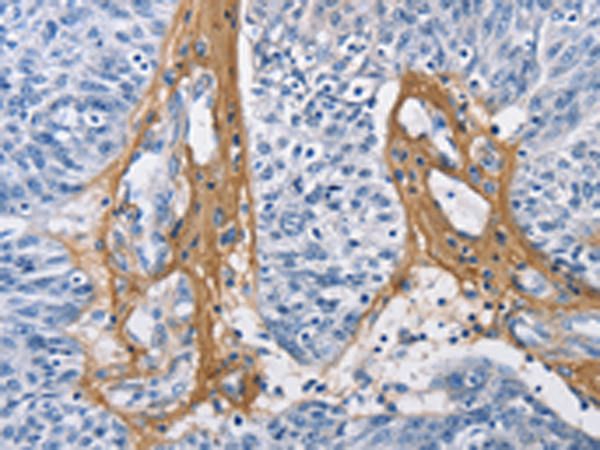

分类: 科研抗体货号: P07217别名: EB1; SCAF1; SCAFI; SIG81; COX7AR; COX7RP应用: WB,IHC反应种属: Human, Mouse

分类: 科研抗体货号: P07218别名: COX11P应用: WB,IHC反应种属: Human, Mouse

分类: 科研抗体货号: P07216别名: NOC4, COX4NB, C16orf2, C16orf4, FAM158B应用: WB,IHC反应种属: Human, Mouse, Rat

分类: 科研抗体货号: P07243别名: DCIR; LLIR; CD367; DDB27; CLECSF6; HDCGC13P应用: WB,IHC反应种属: Human

分类: 科研抗体货号: P07239别名: HLP; CP33; CP34; CYP3A; NF-25; CYP3A3; P450C3; CYPIIIA3; CYPIIIA4; P450PCN1应用: WB,IHC反应种属: Human

分类: 科研抗体货号: P07212别名: AOM; ANFH; SEDC; STL1; COL11A3应用: WB,IHC反应种属: Human, Mouse, Rat

分类: 科研抗体货号: P07237别名: AHH, AHRR, CP11, CYP1, P1-450, P450-C, P450DX应用: WB,IHC反应种属: Human, Mouse, Rat